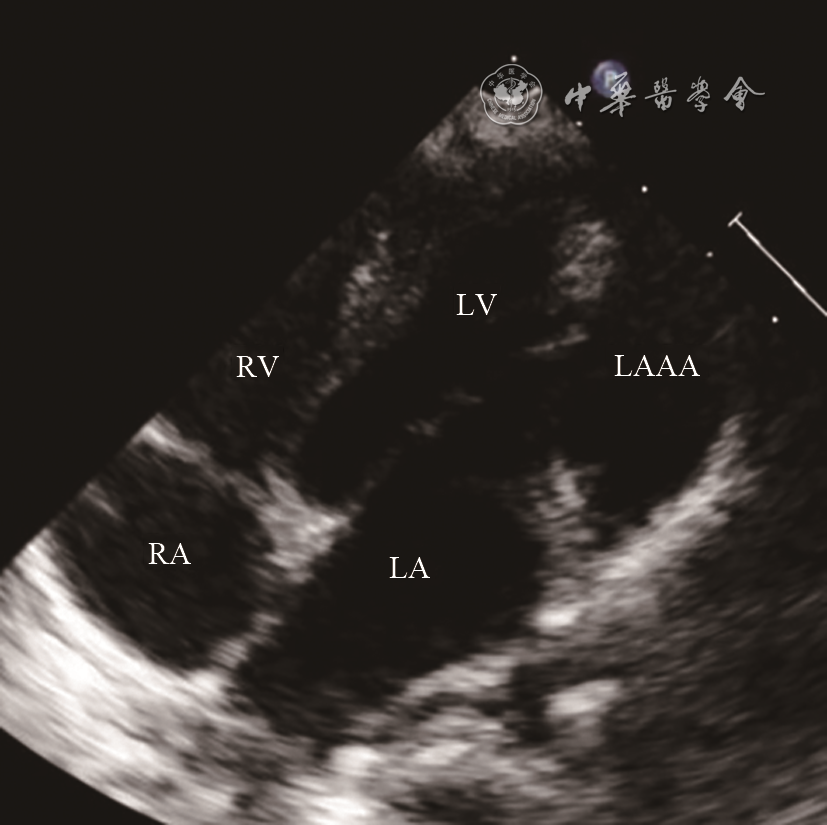

9例患者均经超声心动图检查诊断为LAAA,表现为:(1)四腔心、心底短轴、剑突下等切面二维超声图像可见左心室游离壁外囊状无回声结构,为LAAA;(2)LAAA与左心房交通(图1);(3)彩色多普勒可见LAAA与左心房间血流信号往返(图2);(4)巨大LAAA可压迫左心室或其他毗邻结构(图3);(5)同时可显示合并的其他占位性病变(图4)。

图3 左心耳瘤二维超声图像。图示左心耳瘤压迫左心室致使左心室侧壁向左心室腔内凹陷